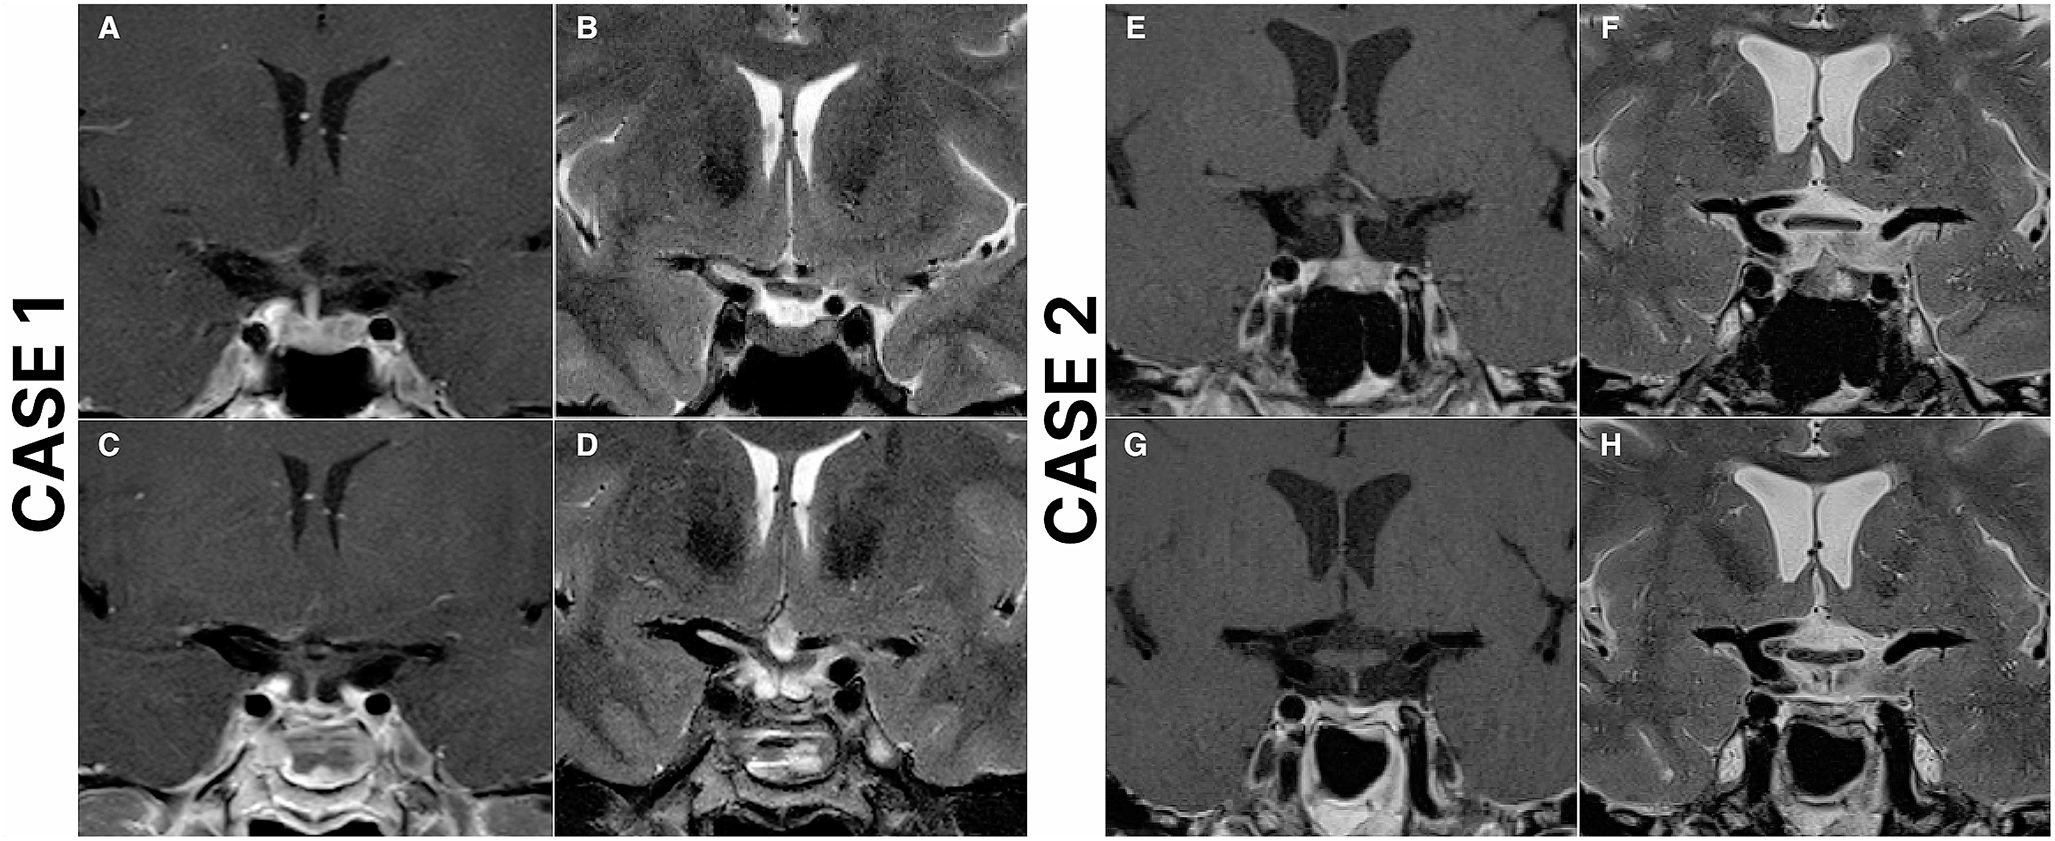

Fig. 2

Case 1: Preoperative and postoperative magnetic resonance imaging (MRI) scans of a 49-year-old female who underwent repeat endoscopic transsphenoidal surgery (ETS) due to recurrent Cushing’s disease and achieved remission. The patient underwent initial surgery 14 years ago at an outside institution. Preoperative T2 (A), and T1 contrast-enhanced (B) MRI scans demonstrate a right-sided pituitary adenoma. Postoperative T2 (C), and T1 contrast-enhanced (D) MRI scans demonstrate total resection of the adenoma. Case 2: Preoperative and postoperative magnetic resonance imaging (MRI) scans of a 53-year-old female who underwent repeat endoscopic transsphenoidal surgery (ETS) due to recurrent Cushing’s disease and achieved remission. The patient underwent initial surgery 3 years ago at an outside institution. Preoperative T2 (E), and T1 contrast-enhanced (F) MRI scans demonstrate a left-sided pituitary adenoma, in close relation to ICA. Postoperative T2 (G), and T1 contrast-enhanced (H) MRI scans demonstrate total resection of the adenoma